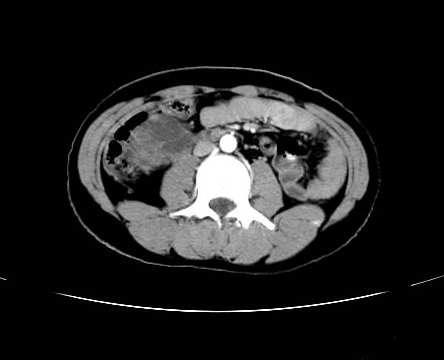

女 16岁  右上腹痛一天,无其他不适

肿块最大径位于十二指肠降段与水平段移行处,并且与肝脏压迹呈“0”形征,可以考虑位于肝外并与胃肠道关系紧密,考虑胃肠道间质瘤(gist)可能较大,须除外神经节起源肿瘤。

肿块与十二指肠关系密切,支持间质瘤诊断.肝脏与结肠均为受压改变.

右下腹巨大肿快,密度不均匀,内见坏死低密度区,边界清楚,与周边胀器明显有分界,未见强化,多考虑来源于间叶组织的良性肿物.

我坚决反对您的观点,该病例定位:横结肠肝曲与升结肠之间的肠系膜及部分肠壁。请看下图:

病灶巨大,少部分向肠腔内生长,大部分向长腔外生长。其密度不均匀,增强显示明显不均匀强化,并见有大片状始终不强化的不规则坏死液化区。虽然病灶中上部形态尚可,病人又如此年轻,但中下部形态、密度、强化特点强烈提示为恶性病灶。综上,我考虑本病例为:恶性胃肠道间质瘤。